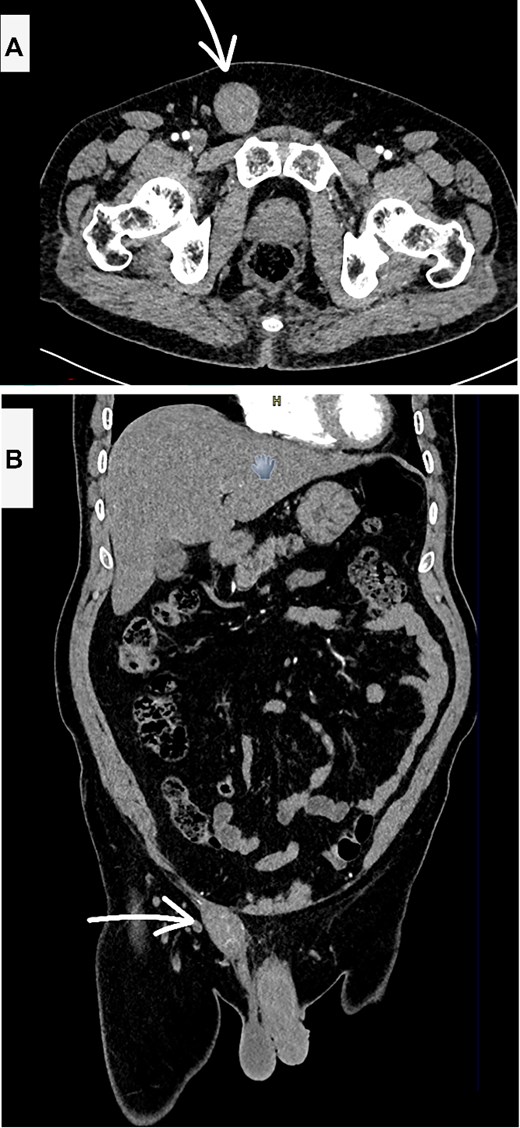

A computed tomography (CT) scan of the abdomen and pelvis with contrast revealed a heterogeneous, enhancing soft tissue mass lesion along the right spermatic cord (Fig. 1). No suspicious lymph nodes, testicular abnormalities, or retroperitoneal masses were identified. The liver, spleen, and lungs were unremarkable.

Contrast enhanced CT scan abdomen and pelvis (A—axial and B—coronal views) showing the suspicious inguinal mass (white arrow).